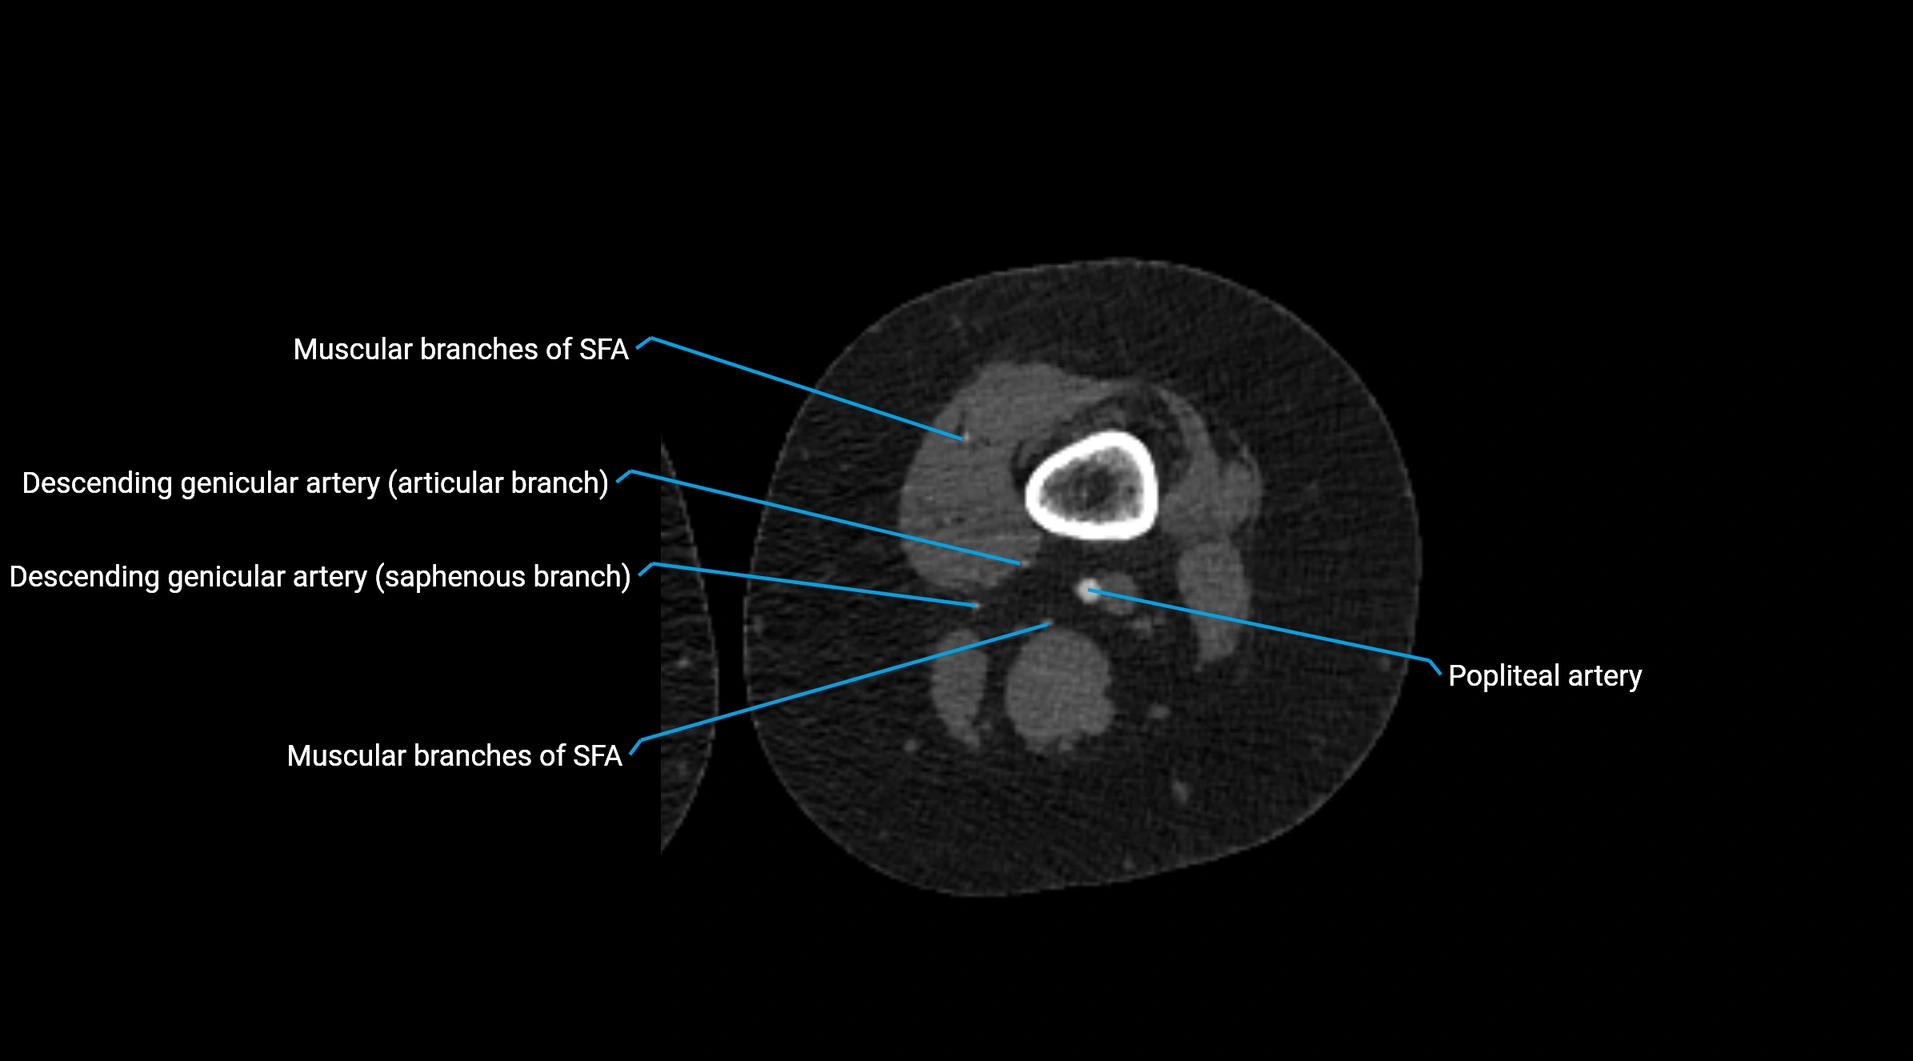

CT images

image